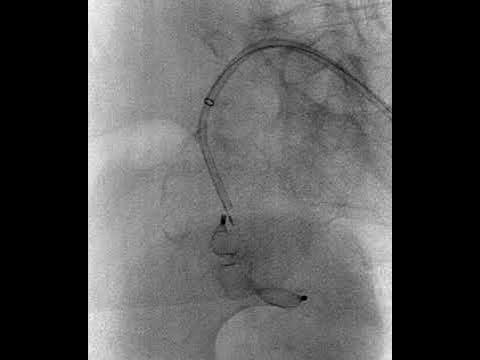

angiografia panoramica con pigtail in aorta in obliqua sinistra e selettiva dell'ipogastrica destra